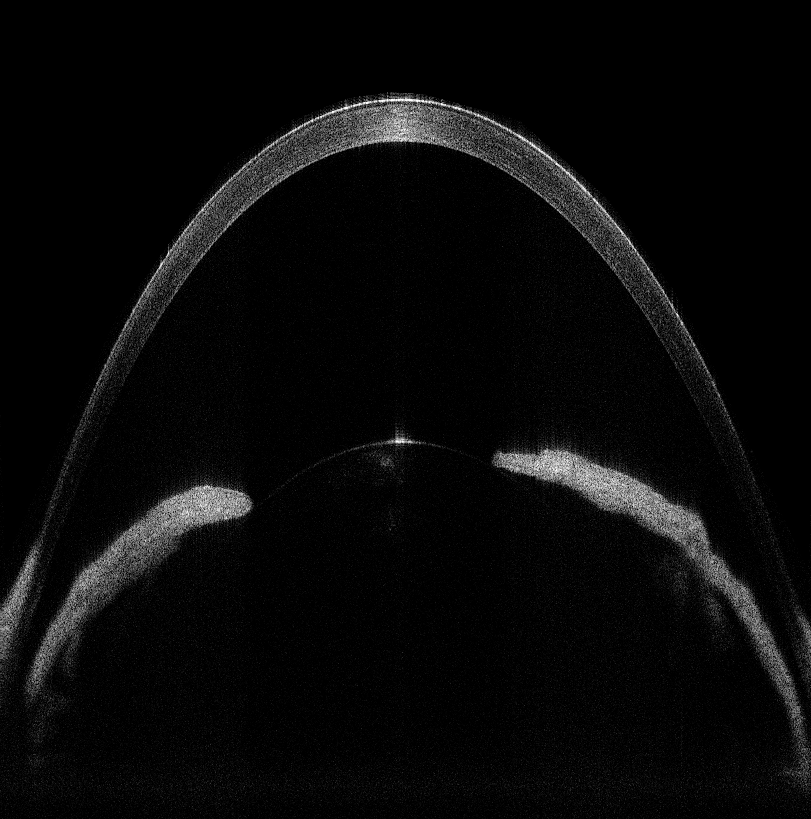

图3  兔眼虹膜OCT图像

采集获得的在体兔眼角膜和在体兔眼虹膜的OCT图像如上图2和图3所示。